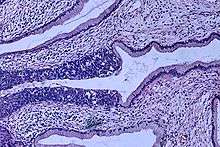

Cervical intraepithelial neoplasia, the potential precursor to cervical cancer, is often diagnosed on examination of cervical biopsies by a pathologist. For premalignant dysplastic changes, cervical intraepithelial neoplasia grading is used.

The naming and histologic classification of cervical carcinoma precursor lesions has changed many times over the 20th century. The World Health Organization classification[38][39] system was descriptive of the lesions, naming them mild, moderate, or severe dysplasia or carcinoma in situ (CIS). The term, cervical intraepithelial neoplasia (CIN) was developed to place emphasis on the spectrum of abnormality in these lesions, and to help standardise treatment.[39] It classifies mild dysplasia as CIN1, moderate dysplasia as CIN2, and severe dysplasia and CIS as CIN3. More recently, CIN2 and CIN3 have been combined into CIN2/3. These results are what a pathologist might report from a biopsy.

These should not be confused with the Bethesda system terms for Pap smear (cytopathology) results. Among the Bethesda results: Low-grade Squamous Intraepithelial Lesion (LSIL) and High-grade Squamous Intraepithelial Lesion (HSIL). An LSIL Pap may correspond to CIN1, and HSIL may correspond to CIN2 and CIN3,[39] however they are results of different tests, and the Pap smear results need not match the histologic findings.